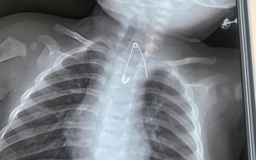

Đi làm răng, kim chọc tủy dài 22 mm 'cắm' vào đường thở bé trai 3 tuổi